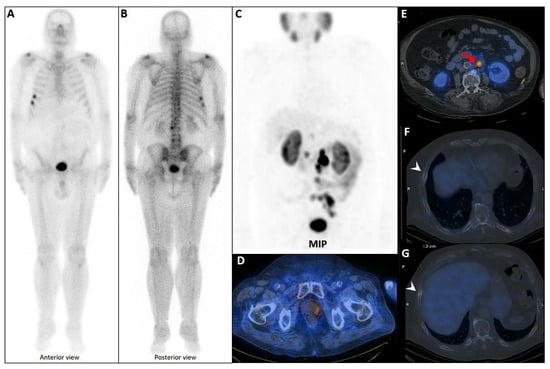

Pleuro-Pulmonary Extramedullary Plasmacytomas in Multiple Myeloma: A 15-Year Experience from a Tertiary Center

Sorina Badelita, Sinziana Barbu, Camelia Dobrea, Cerasela Jardan, Monica Popescu, Codruta Delia Popa, Claudia Toma, Larisa Zidaru, Mihai Emanuel Himcinschi, Horia Mihail Sandu, Didona Vasilache, Adelina Vlad and Daniel Coriu

Background/Objectives: Extramedullary involvement in multiple myeloma represents an aggressive disease phenotype, associated with reduced survival and an unfavorable prognosis. Thoracic manifestations are rare and remain poorly characterized in the literature. Methods: We conducted a retrospective, single-center study at the Fundeni Clinical Institute, including patients diagnosed with multiple myeloma between February 2010 and February 2025. The study cohort consisted of 34 patients with infiltration of the pulmonary parenchyma, pleura, or the presence of myelomatous pleural effusion. Diagnosis was confirmed using a combination of imaging modalities (computed tomography or magnetic resonance imaging), cytological examination, immunophenotyping, and histopathological confirmation whenever feasible. Results: Out of a total of 2012 patients with multiple myeloma, the incidence of pleuro-pulmonary extramedullary involvement was 1.6%. The median age at diagnosis was 58 years. Pleuro-pulmonary disease was present at initial diagnosis in 26.5% of cases, while 73.5% developed it at relapse. The most common presentation involved combined pleural involvement and myelomatous effusion (70.6%). Adverse prognostic markers included elevated β2-microglobulin levels (in over 80% of cases) and increased lactate dehydrogenase (LDH) in approximately 50%. Cytogenetic abnormalities such as del(17p), t(4;14), t(14;16), t(11;14), and 1q gain were identified. The median overall survival (OS) from the diagnosis of pleuro-pulmonary extramedullary disease was 16 months, with a 2-year survival rate of 25%. No patient survived beyond 5 years. The median progression-free survival (PFS) was 9 months. Conclusions: Our findings confirm the aggressive clinical course and poor prognosis of these disease manifestations, mainly when they occur at relapse. In the absence of standardized treatment guidelines, individualizing therapy and accessing novel strategies may be essential for improving patient survival.

Full article